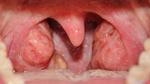

تُعرّف اللوزتين (بالإنجليزية: Tonsils) على أنّهما زوج من الأنسجة اللينة، التي تقع إلى الخلف من الحنجرة، وتتكون من أنسجة تُشبه إلى حدّ كبير الأنسجة المكونة للغدد الليمفاوية (بالإنجليزية: Lymph nodes)، وتكون مغطاة بنسيج مخاطي وردي يُشبه النسيج الذي يُبطّن منطقة داخل الفم، وتجدر الإشارة إلى أنّ اللوزتين تُعدّان جزءاً مهماً من الجهاز اللمفاوي الذي يُساعد على مكافة العدوى والبكتيريا، وقد تتعرض اللوزتين في بعض الحالات للالتهاب وبالتالي حدوث انتفاخ بهما، ومن الجدير بالذكر أنّ هذا الالتهاب قد يحدث في أي مرحلة زمنية، ولكنَّ فئة الأطفال من مرحلة ما قبل الذهاب إلى المدرسة إلى منتصف مرحلة المراهقة تكون أكثر عرضة للإصابة بالتهاب اللوزتين.[1][2]

- احمرار وانتفاخ اللوزتين.

- وجود بقع صفراء أو بيضاء على اللوزتين.